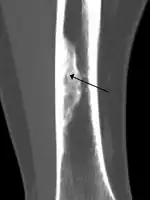

An ossified non-ossifying fibroma on CT